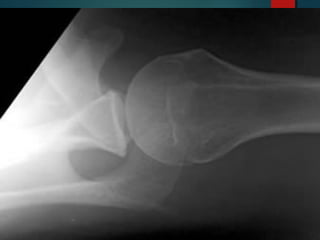

Axillary view represents the “gold standard” in

radiographic assessment of location of the humeral

head relative to the glenoid cavity.